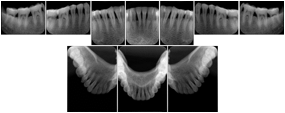

3. A patient in rural Minnesota experiences sudden vision loss and goes to a general ophthalmologist, who acquires OCT images and forwards them electronically along with a Structured Display to a retina specialist six travel hours away. The retina specialist is able to view the images in the standard layout that he is comfortable with, and to confirm that the patient has a choroidal neovascular membrane. He determines that is would be worthwhile for the patient to travel for treatment.

OCT Retinal Study with Cross Section and Navigation Structured Display

Figure OO-4. OCT Retinal Study with Cross Section and Navigation Structured Display